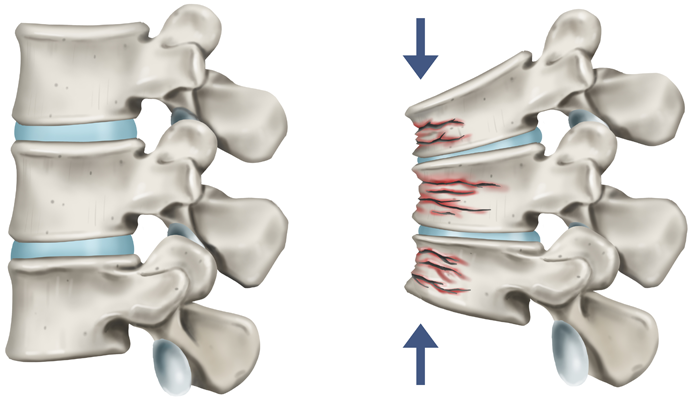

평상시 잘 사용하지 않던 몸을 사납게 사용하는 경우, 작은 바깥쪽 충격에도 뼈가 부러지는 등 골절을 겪기 쉬운 상태가 되요. 골절은 아무리 미세하고 약한 정도라도, 일상생활에 부담을 주고요.